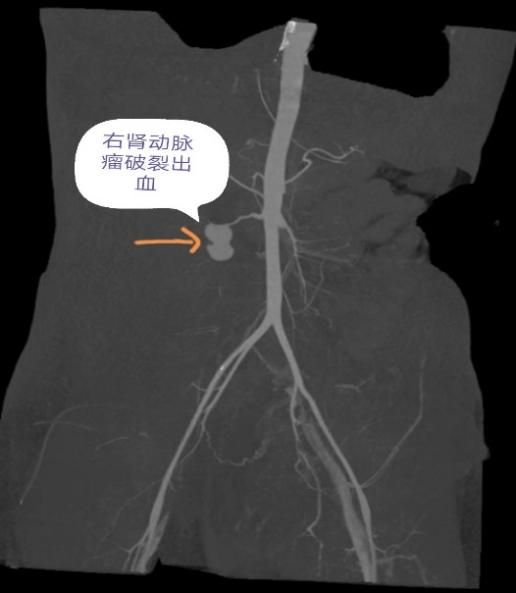

“当天晚上8点多,她转来时已面色惨白、右侧腰部剧烈疼痛,心率达到140次/分,存在失血性休克的可能。”据接诊的广医三院产科医生柯彩萍介绍,当时情况危急,产科与急诊科立即启动绿色通道,马上为丽丽输血输液,做腹部CT检查。结果让人心惊——医生发现丽丽右肾周间隙有大小约为11*8*5厘米的巨大血肿,盆腔、腹腔都有积液(图1)。腹部检查提示右肾动脉近肾门处有2厘米的动脉瘤破裂出血,而且右肾周间隙也有巨大血肿(图2)。

(图2)CTA提示丽丽右肾动脉近肾门处动脉瘤破裂出血